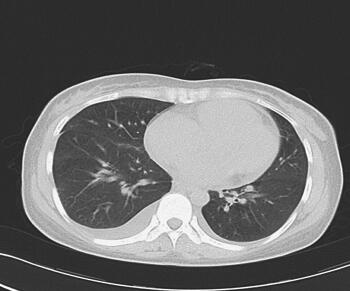

诊治经过:入院后查血常规示:WBC 11.3×109/L,N 77.3%,Hb 127g/L,PLT 202×109/L;生化:LDH 545IU/L,Ca2+ 1.9mmol/L,余未见异常;cTnI 0.20ng/ml,BNP 1315pg/ml;凝血:PT 15.4秒,APTT 36.5秒,INR 1.28,FIB 4.1g/L,D-二聚体0.93μg/ml;抗“O”47.5IU/ml;血沉:5mm/h,入院后第1天予青霉素、异帕米星联合抗感染,硝酸甘油、利尿剂减轻心脏负荷,营养心肌等治疗。入院第3天查肺部CT(图1),入院第4天查心脏彩超。入院第5天请心外科会诊,转心外科手术治疗。入院第8天在全麻CPB下行“左心房黏液瘤切除术”。手术顺利,术后继续给予阿莫西林-舒巴坦钠抗感染、营养心肌等对症处理,患者恢复顺利,复查血常规、生化大致正常,复查心电图、胸片未见明显异常,入院后第15天复查心脏彩超示左心房黏液瘤术后,左心房内未见异常征象,二尖瓣反流(+~++),心包少量积液。入院第17天出院。但该患者出院后肿瘤复发,术后半年内死亡。

图1 胸部CT示双肺感染,双侧胸腔少量积液,右上肺局限性肺气肿

3.血象高,肌钙蛋白、BNP升高,胸部CT示双肺感染,双侧胸腔少量积液,右上肺局限性肺气肿。